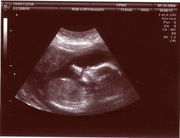

Sonograph showing the image of a fetal head in the womb

Obstetrical ultrasound is commonly used during pregnancy to check on the development of the fetus.